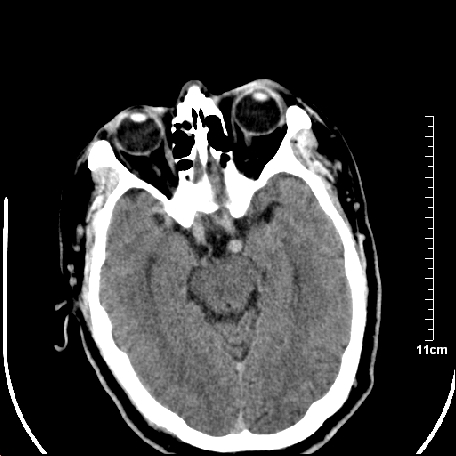

双侧外侧裂,左侧脑沟见高密度结节影,边清,还有鞍上池层面密度也高

脑血管硬化?高血红蛋白症?

2.老年脑,基底动脉硬化迂曲。

基底动脉硬化迂曲。高血红蛋白血症。